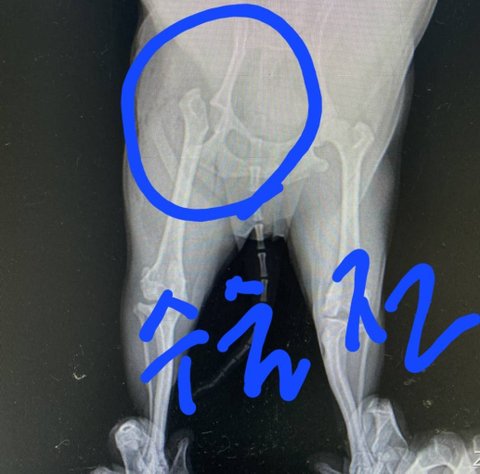

저희강아지가 대퇴골골절과 인대가 끊어져

받으니 외력에의한 대퇴골골절과 인대끊어짐소견으로 보인다며 바로 수술해야 한다해서 수술진행하고 이틀뒤 퇴원했습니다.